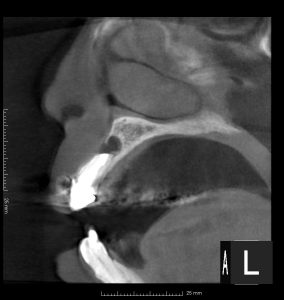

レントゲンを見てみよう。

(術前のレントゲン、CT)

右上2、左上1、左上2に根尖病変がある。

また、左右2番の根尖部に圧痛を認めた。

過去の根管治療ではラバーダムは使用していなかったとのこと。

4本の根管治療のうち、3本が失敗し、根尖病変ができている。